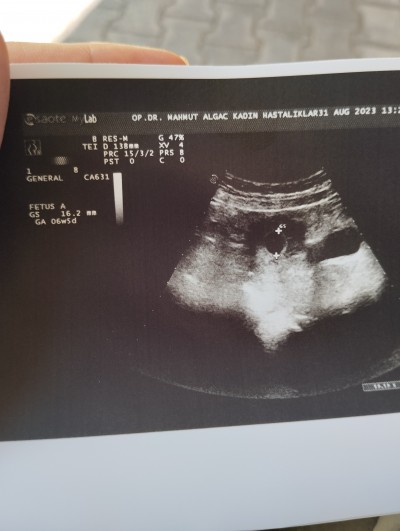

31 Ağustos 2023 Hamilelik Dönemi Genel kategorisinde (351 puan) sordu

Merhaba doktor olumsuz komusmadi bir hafta sonra gel kalp için bakalım dedi olumsuz ben konuştum demedi erken daha şuan dedi haftalık bile sorduğumda birşey diyemem dedi 5 gibi dedi sizce

Benden soylemek istemedim korkum vardı ama duyuldu işte .doktor olumsuz birşey demdi 6 mm Ken 16 mm olmuş iki haftadan rabim kucağımıza almamızı nasip etsin tşk ederim